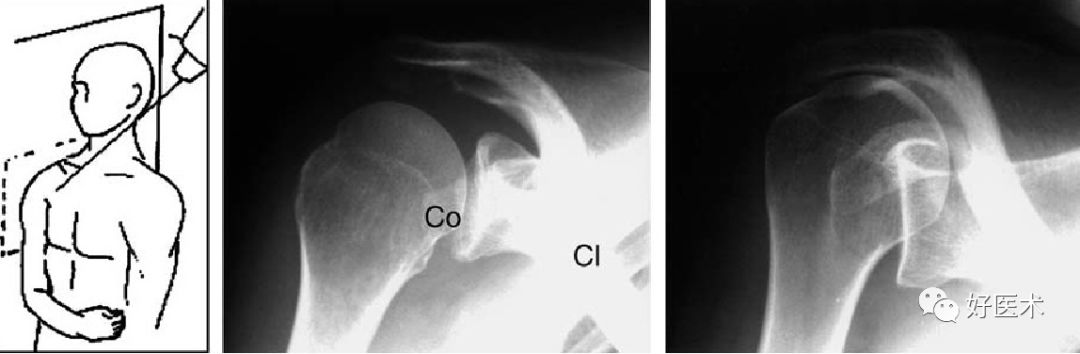

Bernageau位

肩关节前颅位